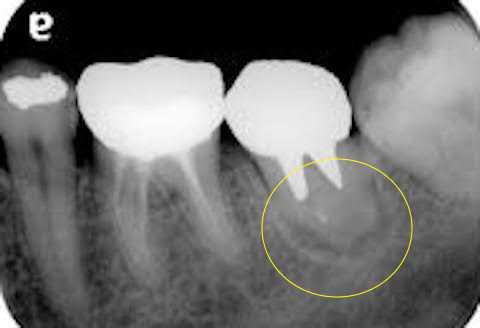

40代男性、右下6、インレー2次カリエス、自発痛ーこの方は咬合性外傷があるのだが、自覚はない。2次カリエスにはなるし、歯茎部のカリエスにもなる。典型的な咬合性外傷の所見なのだが、ご本人は、は?、という感じだ。この右下6は2015年が最初の治療なのだが、何度か再治療をしている。歯茎部カリエスになる。そしてとうとう近心根が壊死してしまったが、これも自覚症状がない。近心根の陰影が大きくなっていくのが分かると思う。2019/10/262020/10/302021/10/31今日は6年前、2015年の最初の2次カリエスの治療の画像だ。はっきり言って、超絶技巧を要するCR充填だ。この時はストリップスを使用しているが、どうやってやるのか分からないレベルだと思う。では時系列でどうぞこれは次の年の2016年の画像だ。つづく